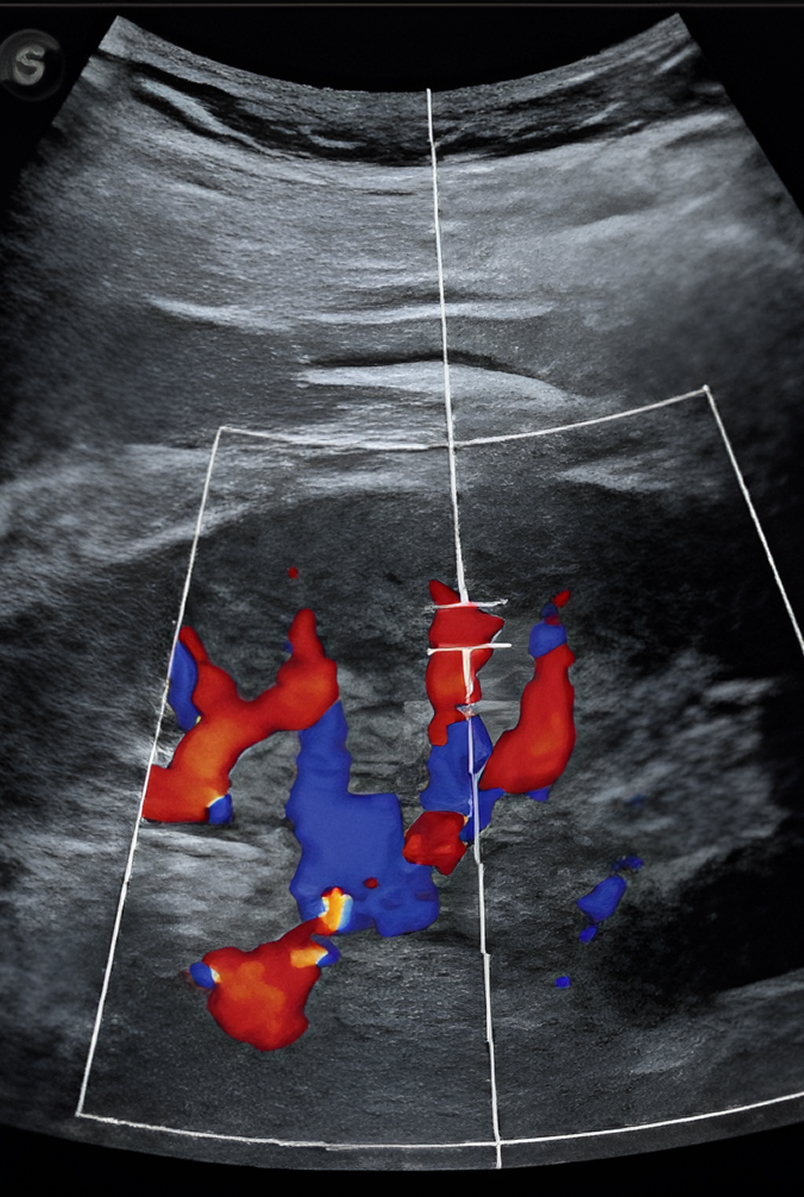

• Diagnóstico preciso y seguimiento mediante valoración ecográfica de la congestión: POCUS, VEXUS y FOCUS.

• Ecografía pulmonar (LUS), vascular (VEXUS), cardíaca (ecocardiografía/FOCUS) y renal para la valoración del estado de congestión tisular y vascular.

Ecografía y doppler renal para valoración

morfológica y vascular renal